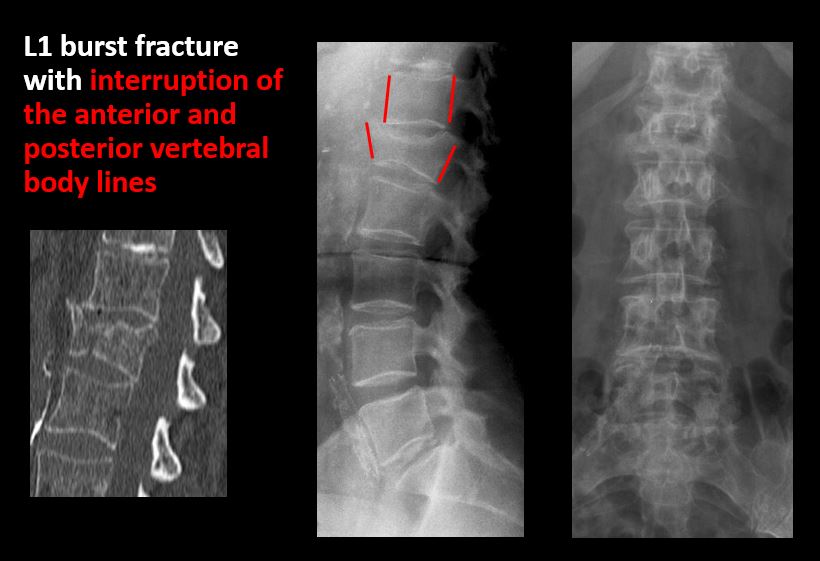

Section 1 Submit Findings CB1239 Findings Technique The thoracolumbar junction and/or the lumbosacral junction is/are not entirely included on the exam. Yes No The exam is over or under penetrated. Yes No The exam is limited by overlying structures, bones or soft tissues, patient positioning, support devices, or motion. Yes No Prevertebral and paravertebral soft tissues The prevertebral or paravertebral soft tissues are abnormal. Yes No Spinal alignment The vertebral bodies are abnormally aligned. Yes No The anterior and posterior vertebral body lines are abnormal or interrupted. Yes No The visualized spinous processes are malaligned or distracted on the AP and/or lateral view(s). Yes No There is reversal or straightening of the normal lordosis or scoliosis of the lumbar spine. Yes No Vertebral bodies, posterior elements and included sacral segments There are more or less than the expected 5 non rib-bearing vertebral bodies. Yes No There is a transitional motion segment at the lumbosacral junction (sacralization of L5 or lumbarization of S1). Yes No There is a fracture or distraction of a vertebral body, transverse or spinous process, or other posterior element. Yes No There is anterior wedging and/or compression of a vertebral body or end plate. Yes No There is an end plate avulsion or other fracture. Yes No There is displacement of a fracture fragment into the soft tissues or spinal canal. Yes No There is lucency or defect of the pars interarticularis from spondylolysis. Yes No There is an abnormality of a pedicle or lamina on the frontal or lateral view. Yes No There is a fracture, erosion, sclerosis, lytic, or blastic lesion of a pedicle or lamina. Yes No There is evidence of a lytic or sclerotic lesion, or disruption of the trabecular pattern of a vertebral body, end plate, or sacrum. Yes No There is a fracture or interruption of the arcuate lines of the sacrum. Yes No There is erosion, sclerosis, narrowing, or other abnormality of a sacral foramen or the SI joints. Yes No There is focal or diffuse abnormal mineralization of the lumbosacral spine. Yes No Disc spaces and facet joints There is distraction or focal widening of a disc space. Yes No There is disc space narrowing with or without erosive or sclerotic changes of the end plates or subchondral bone other than from degenerative change. Yes No There is anterior or posterior spondylolisthesis, subluxation, or rotational abnormality at a disc space. Yes No There is widening, rotational abnormality, or displacement of facets at any motion segment. Yes No There is facet joint narrowing or sclerosis other than from degenerative change. Yes No There is narrowing or encroachment of a neural foramen other than from degenerative change. Yes No There are degenerative changes present that might explain the patient’s symptoms. Yes No Additional soft tissues and bones (lower thorax, abdomen, and pelvis) There is abnormal bowel or bowel gas pattern. Yes No There are gallstones, vascular, renal, pelvic, or other soft tissue calcifications present. Yes No There is free intraperitoneal or retroperitoneal air or other abnormal air in the included chest, abdomen, or pelvis. Yes No The included thoracic spine, ribs, and remainder of the bony pelvis are abnormal. Yes No There is abnormality of the lower chest and/or diaphragm. Yes No There is a foreign body or there are post surgical changes of the bones or soft tissues of the included lower thorax, abdomen, and pelvis. Yes No There is an abnormality or complication of post surgical hardware/device. Yes No N/A There are support lines or tubes in an abnormal position. Yes No Other findings There are other existing conditions that might be contributing to symptoms which can or should be further evaluated non-emergently. Yes No